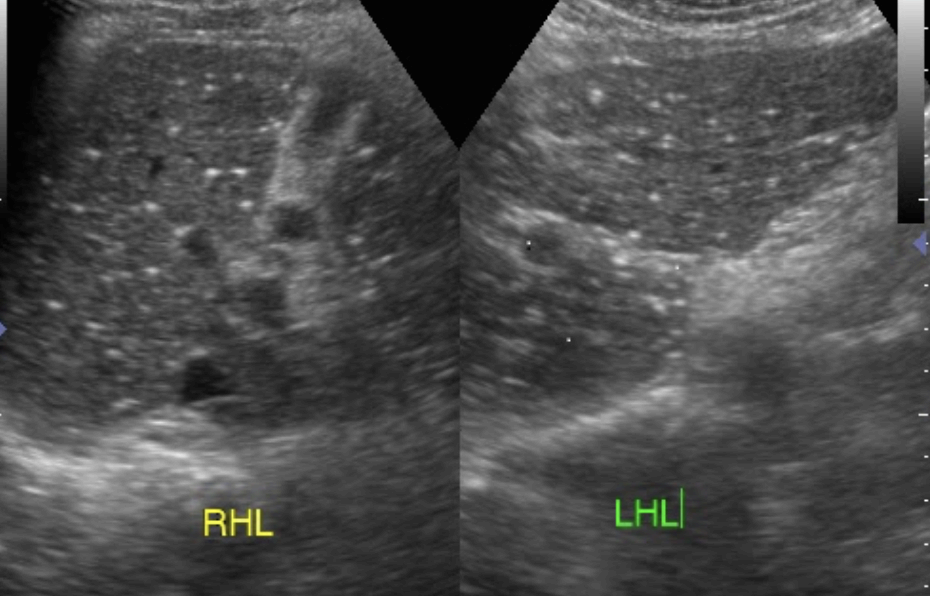

- starry sky appearance (급성간염에서 간실질 에코의 감소와 문맥벽 에코의 증가로 밤하늘의 별과 같이 보이나 진단의 민감도와 특이도는 낮은 편이다.)